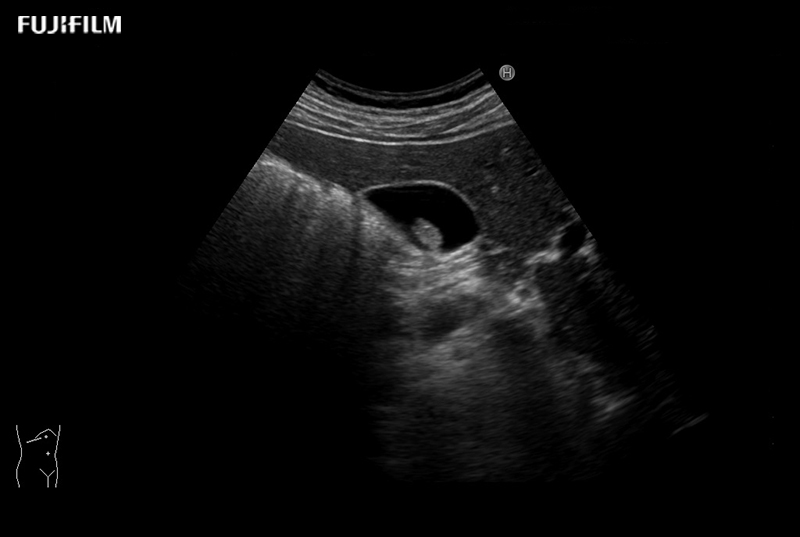

Liver Surgery Procedure using L46K1

Wide-view side-fire “T” transducer for open surgical procedures, providing exceptional near and far-field resolution, as well as trapezoid imaging to further expand visibility.